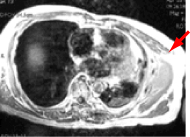

| ●図2-a |